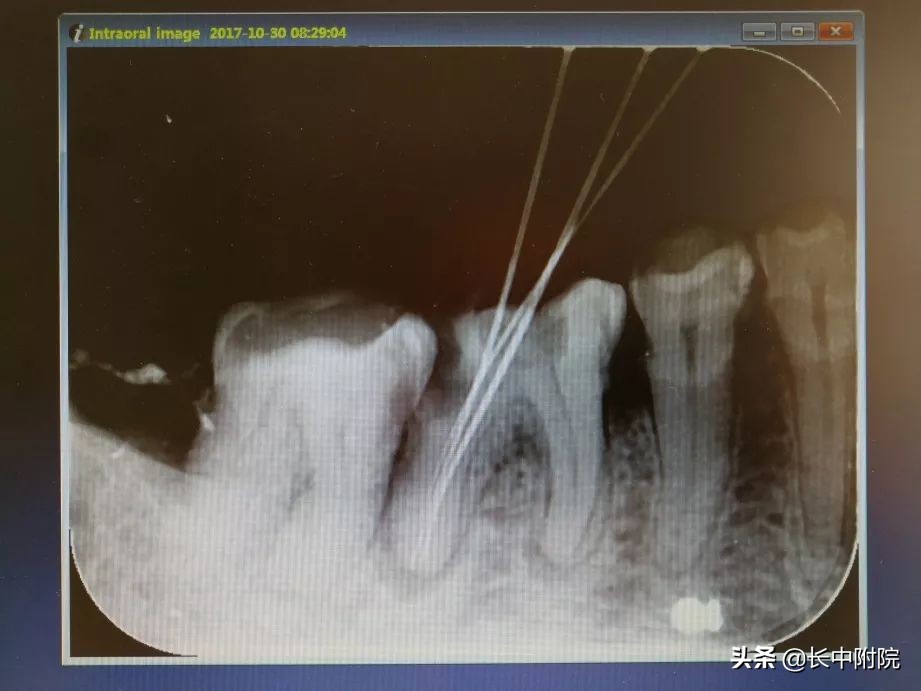

3.确定根管工作长度

应用平行投照X线方法、根管长度测量仪确定根管度,最好插针拍X片。